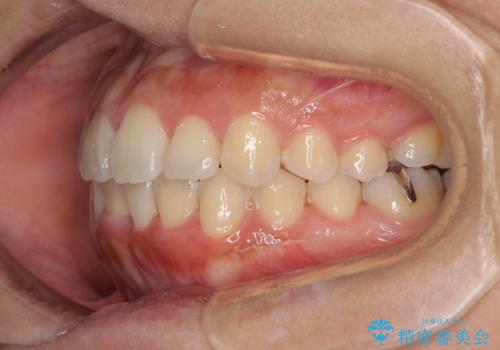

前歯のデコボコをインビザラインでスッキリと

- 上下前歯のデコボコを気にして来院された患者様です。

デコボコを解消する過程で、歯列の拡大により口元が突出する可能性があったため、4本の親知らずを抜歯しておき、歯列全体が後方に移動するように設計し、インビザラインにて矯正治療を行うこととしました。

日々の装着時間をしっかりと守って治療の臨んでくださったため、治療前のシミュレーションに近い形で矯正治療を進めて行くことができました。